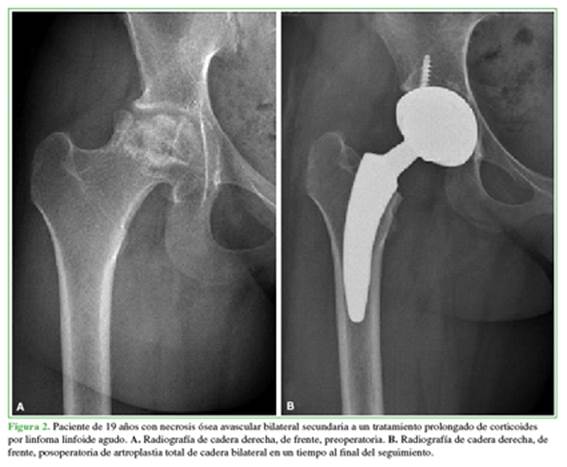

Las causas que llevaron a la indicación de cirugía fueron: tres condrólisis idiopáticas, tres necrosis óseas avasculares (NOA) secundarias a epifisiólisis, dos secuelas de artritis séptica, una secuela de fractura de acetábulo, una displasia del desarrollo con secuela de osteotomía de pelvis fallida y seis casos (las tres bilaterales) de NOA inducidas por tratamiento prolongado de corticoides secundario a enfermedad de Crohn, lupus y leucemia linfoide aguda. En total, nueve (56%) de los casos corresponden a NOA secundaria a diferentes causas (Tabla 2, Figura 2). Ocho (50%) tenían cirugías previas a la ATC (Figura 3).

Después de obtener la aprobación de la junta ética de investigación de la institución, estudiamos retrospectivamente 26 ATC en 23 pacientes <20 años operados entre enero de 2006 y enero de 2021. Se incluyeron solo los casos de ATC con tallo femoral corto no cementados y un seguimiento mínimo de un año. Se excluyó a los pacientes con enfermedad oncológica activa relacionada con la patología, aquellos operados con tallos femorales cementados (8 pacientes) y tallos no cementados de tamaño estándar (2 pacientes). Luego de aplicar los criterios de selección, se excluyó a 10 pacientes; en consecuencia, se incorporaron 13 pacientes (16 caderas) sometidos a ATC primaria con un vástago corto no cementado tipo 2B con fijación cervico-metafisaria (MiniHipTM, Corin, Cirencester, Reino Unido) (Figura 1).11 Los datos demográficos de la serie se detallan en la Tabla 1.